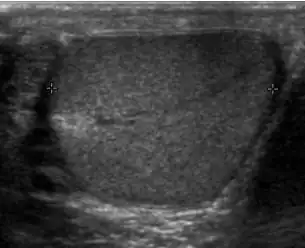

Patients with testicular lymphoma are usually old aged around 60 years of age, present with painless testicular enlargement and less commonly with other systemic symptoms such as weight loss, anorexia, fever and weakness. Bilateral testicle involvements are common and occur in 8.5% to 18% of cases. At sonography, most lymphomas are homogeneous and diffusely replace the testis [Fig. 7]. However focal hypoechoic lesions can occur, hemorrhage and necrosis are rare. At times, the sonographic appearance of lymphoma is indistinguishable from that of the germ cell tumors [Fig. 8], then the patient's age at presentation, symptoms, and medical history, as well as multiplicity and bilaterality of the lesions, are all important factors in making the appropriate diagnosis.

Primary leukemia of the testis is rare. However, due to the presence of blood-testis barrier, chemotherapeutic agents are unable to reach the testis, hence in boys with acute lymphoblastic leukemia, testicular involvement is reported in 5% to 10% of patients, with the majority found during clinical remission. The sonographic appearance of leukemia of the testis can be quite varied, as the tumors may be unilateral or bilateral, diffuse or focal, hypoechoic or hyperechoic. These findings are usually indistinguishable from that of the lymphoma [Fig. 9].

Fig. 9. Leukemia. Diffuse hypoechoic infiltrative lesions are seen involving the whole testis, indistinguishable from that of the lymphoma.